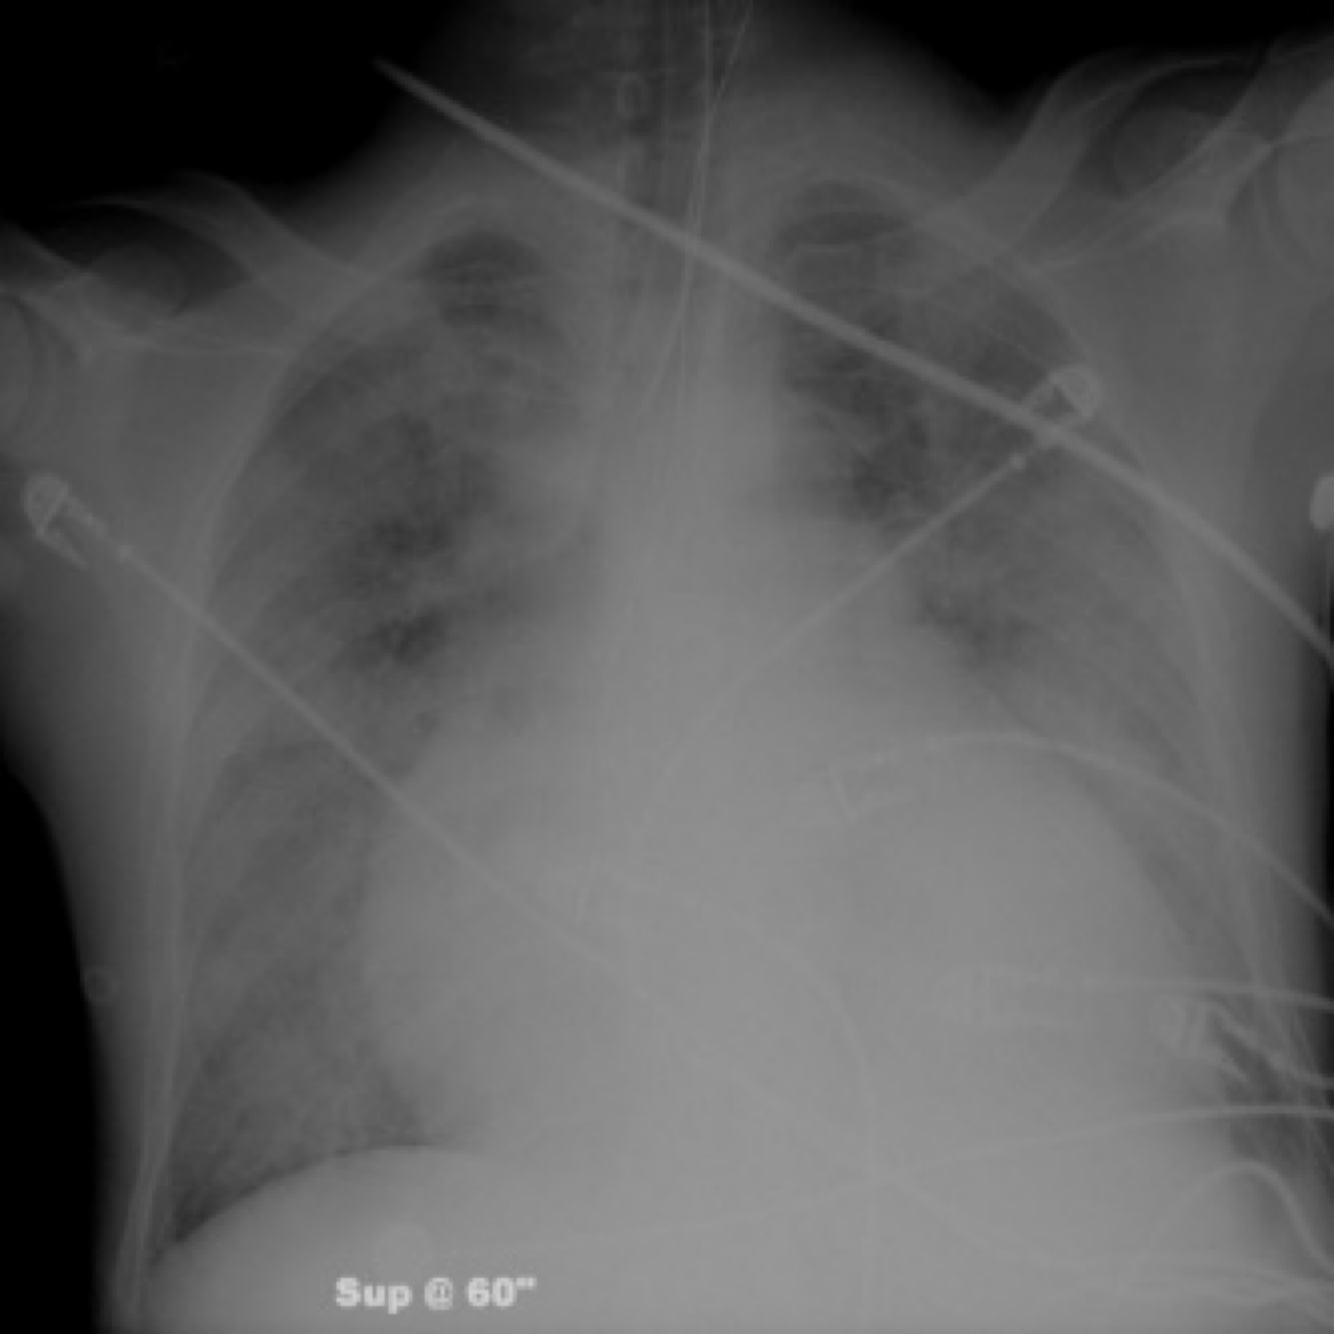

right pleural effusion shown on x-ray,